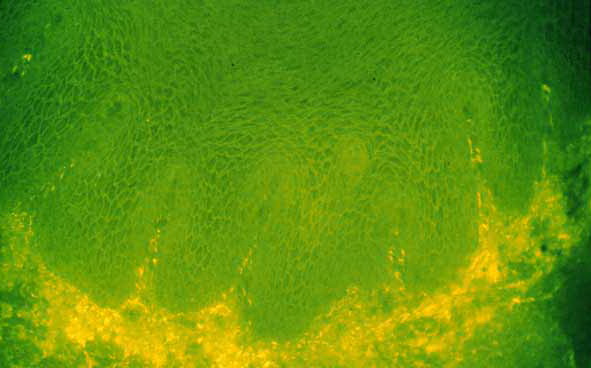

Immunofluorescence (IF) Testing.

The edge of a blister with intact surrounding normal skin, uninvolved skin adjacent to a blister, or adjacent erythematous skin should be supplied for study. The tissue may be snap-frozen or transported in Michel’s medium. DIF testing is a very reliable and sensitive diagnostic test for pemphigus vulgaris, in that it demonstrates lacelike IgG in the squamous intercellularlcell surface areas in up to 95% of cases, including early cases and those with very few lesions, and in up to 100% of cases with active disease . It remains positive, often for many years after clinical disease has subsided. In late lesions, when acantholysis is well developed, the lacelike intercellularlcell surface pattern of IgG may become dotlike, paralleling electron microscopic findings and correlating with aggregation of desmosomes on the cell surface. Negative DIF findings when the patient is in